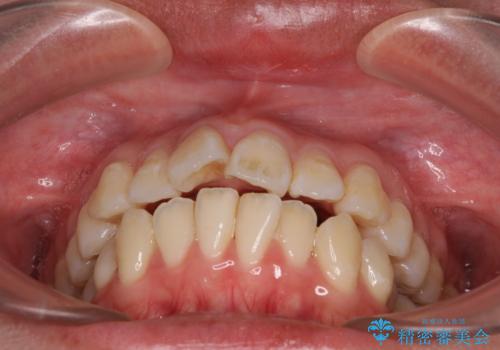

- 上下の出っ歯を気にして来院された患者様です。

口元を積極的に引っ込めるために、上下左右の第一小臼歯を4本抜歯することとしました。

また、上下前歯は舌の突出癖による開咬となっていたため、舌のトレーニングを徹底するよう指示しました。

舌突出癖の改善トレーニングは、仕上がり、治療期間、そして治療後の後戻りに大きな影響を及ぼします。

トレーニングをしっかりと行っていただいたため、スッキリとした口元に仕上がりました。